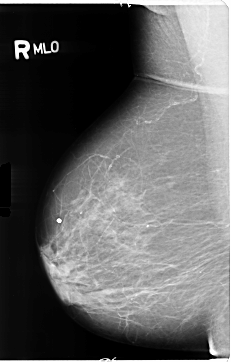

B_3108_1.RIGHT_MLO

RIGHT_MLO LINES 4696 PIXELS_PER_LINE 3000 BITS_PER_PIXEL 12 RESOLUTION 50 NON_OVERLAY